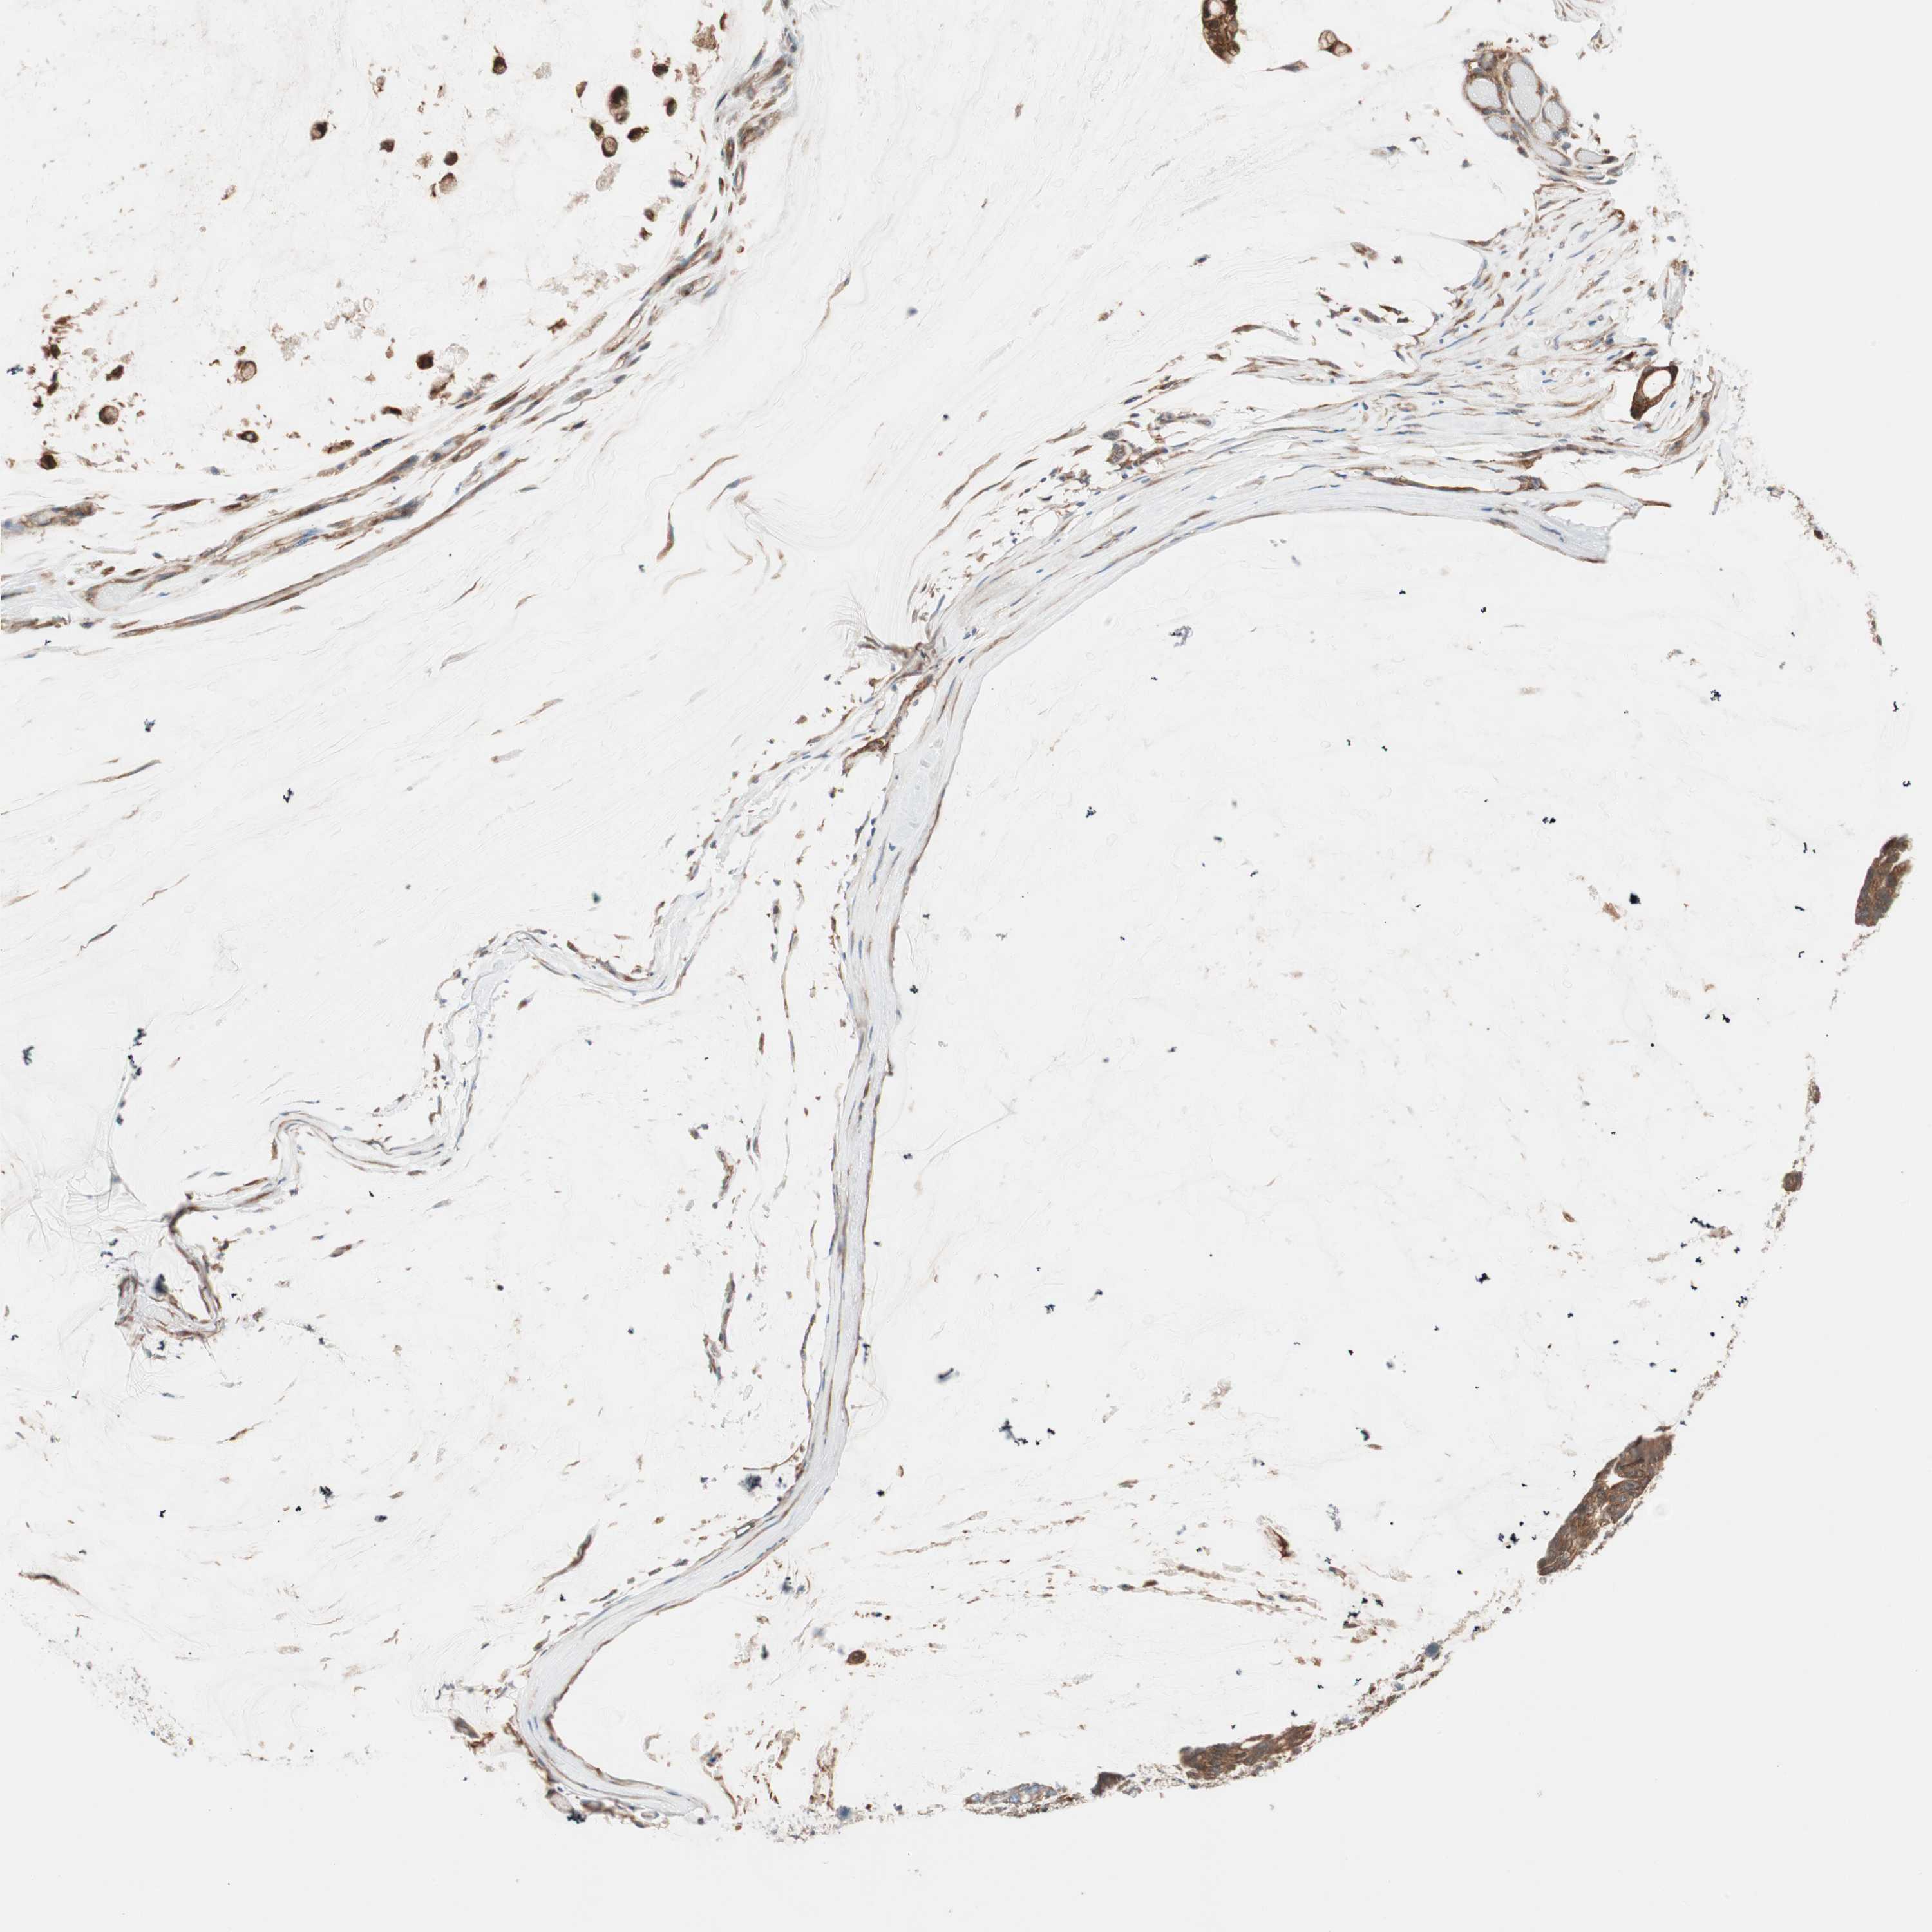

OVARIAN CANCER - Protein expressioni

A mouse-over function shows sample information and annotation data. Click on an image to view it in a full screen mode. Samples can be filtered based on level of antibody staining by selecting one or several of the following categories: high, medium, low and not detected. The assay and annotation is described here.

Note that samples used for immunohistochemistry by the Human Protein Atlas do not correspond to samples in the TCGA dataset.

Antibody stainingi

Antibody staining in the annotated cell types in the current human tissue is reported as not detected, low, medium, or high, based on conventional immunohistochemistry profiling in selected tissues. This score is based on the combination of the staining intensity and fraction of stained cells.

Each image is clickable and will lead to virtual microscopy that enables deeper exploration of all samples and also displays staining intensity scores, fraction scores and subcellular localization as well as patient and tissue information for each sample.

Antibody HPA005750

Antibody CAB005399

Cystadenocarcinoma, serous, NOS

Carcinoma, endometroid

Cystadenocarcinoma, mucinous, NOS

Carcinoma, NOS